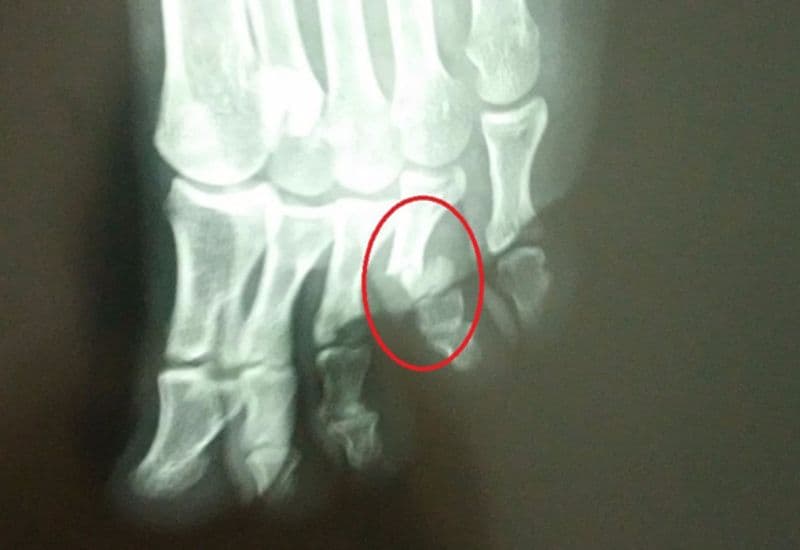

3.2 Chụp X-quang

Chụp X-quang là phương pháp chẩn đoán quan trọng nhất trong việc xác định gãy xương. Hình ảnh X-quang sẽ giúp bác sĩ nhận diện chính xác vị trí và mức độ gãy xương ngón chân của bạn.